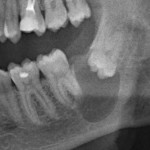

Обязательным обследованием для планирования операции синуслифтинга является компьютерная томография (КЛКТ). В верхнечелюстной пазухе могут быть перегородки и карманы, на обычном панорамном снимке увидеть их сложно. Также КЛКТ даёт возможность измерить расстояние АБ (с этого мы с вами начинали статью):

и рассчитать примерное количество биоматериала, требующееся для заполнения субантрального пространства. И, если представить основные параметры дна верхнечелюстной пазухи как трапецию, то объем графта можно рассчитать по формуле:

Например, если нам необходимо поднять дно верхнечелюстного синуса на 10 мм в пределах одного зуба при ширине дна в 6 мм и ширине верхнечелюстной пазухи 15 мм, то для заполнения такого объёма нам потребуется, приблизительно 1050 куб мм (1,05 куб см.) графта. В пересчете на массу, Geistlich Bio-Oss L мы получим 0,33g — одной стандартной упаковки 0.5g более, чем достаточно.

Разумеется, это очень приблизительные расчёты, они не учитывают рельеф дна, объем части имплантата, выходящей в субантральное пространство. Но они, по крайней мере, дают представление о том, что не нужно заталкивать в субантральную полость три грамма материала, если речь идёт о синуслифтинге в области одного-двух зубов.

Еще КЛКТ позволяет подобрать и позиционировать имплантаты, если планируется их установка одновременно с синуслифтингом. Как это сделать правильно — читайте здесь>>.